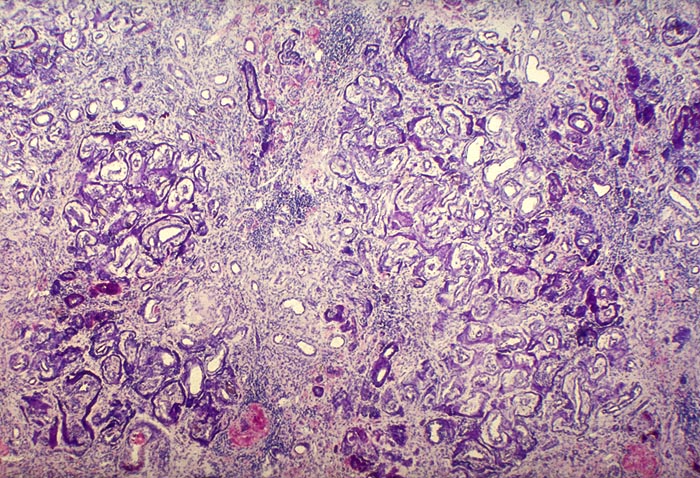

AP/ Nephrokalzinose

Nephrokalzinose

Niere

Pathologischer Befund